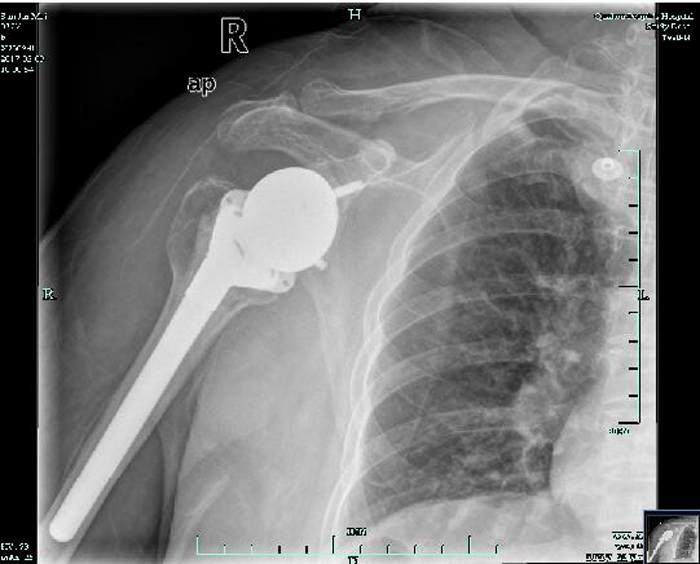

術(shù)后復(fù)查片

??? 經(jīng)過(guò)醫(yī)生的細(xì)致檢查,發(fā)現(xiàn)孫阿婆患有肱骨頭壞死、巨大肩袖損傷及肩關(guān)節(jié)骨性關(guān)節(jié)炎。5月7日,骨科運(yùn)動(dòng)醫(yī)學(xué)關(guān)節(jié)外科團(tuán)隊(duì)在何飛熊主任的帶領(lǐng)下,為孫阿婆成功實(shí)施了逆置型肩關(guān)節(jié)置換手術(shù)。

??? 該手術(shù)是我市開(kāi)展逆置型肩關(guān)節(jié)置換手術(shù)的第一例。孫阿婆裝上的“假肩膀”,其實(shí)是用鈦合金等材料制成的肩關(guān)節(jié)假體,因?yàn)槭前仓迷诠穷^里的,所以從外觀上看不出來(lái),也不會(huì)給她的日常生活造成不便。